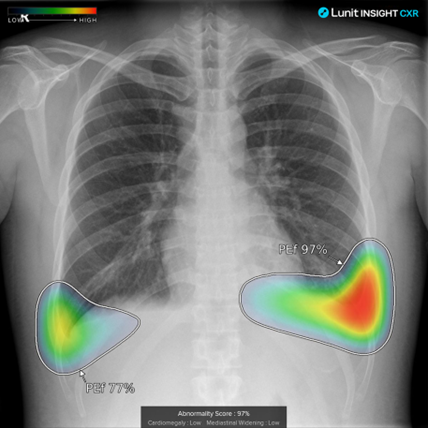

그림1.png [그림1] 출처 : Lunit Inc.

INSIGHT CXR은 흉부 엑스레이 이미지를 분석하는 소프트웨어다. 이 소프트웨어는 흉부 엑스레이 이미지에서 비정상적인 소견을 감지하고, 이를 의료진에게 알려준다. 주로 폐 결절, 폐렴, 흉수(가슴 안의 액체 축적), 폐기종 등의 병변을 탐지하고, 병변의 위치, 존재 가능성을 보여준다.